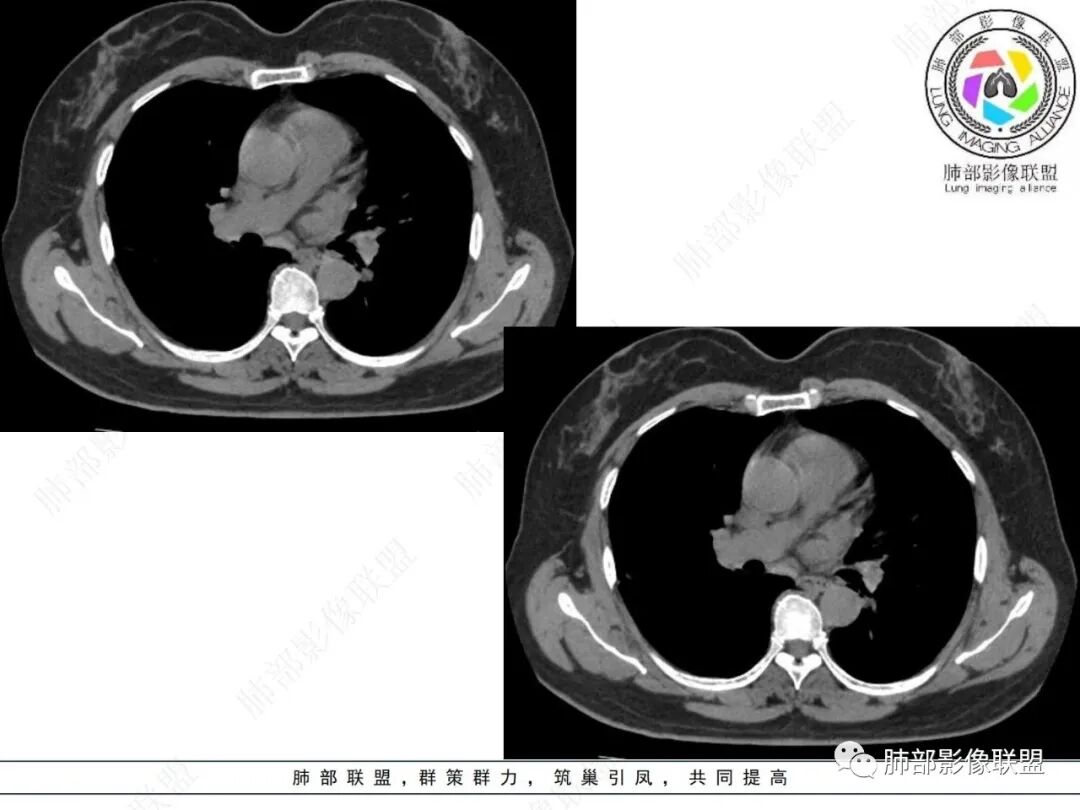

2.影像特点:

右肺上叶胸膜下混合磨玻璃团片影。

周围磨玻璃部分间杂条索状高密度区,密度欠均匀(可疑重力分布趋势),其磨玻璃影边界大多较清楚或可分辨,部分“L型”边缘,提示小叶间隔阻挡可能。血管穿行自如,可疑远端支气管进入。

实性部分较密实,不规则,隐约见棘突或刺状突起,未见钙化、空洞或液化区,实性边缘可见斑状略低密度间隙(借用王兆宇老师课件,称其呈“松软”的形态)。动脉期实性部分较明显不均匀强化,如果有完整增强图,还可以观察内部血管情况。

纵隔窗相对肺窗病灶相对小,仅部分实性影呈现。病灶张力不高,相邻胸膜增厚(糊墙),未见明显胸膜牵拉凹陷。

未见卫星病灶,远处未见磨玻璃结节影。

双肺门及纵隔未见明显增大淋巴结。心包及胸腔未见积液。